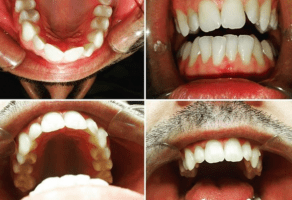

Vaš osmeh je naš uspeh

Naši profesionalni stomatolozi, pobrinuće se da Vaš osmeh bude besprekoran i da Vaši zubi budu zdravi. Svaki član našeg tima nastoji da Vam obezbedi pre svega vrhunsku uslugu,

ali i da Vam omogući prijatno i ugodno iskustvo.

Dental Studio DR O nastoji ka ispunjenju i prevazilaženju očekivanja pacijenata. Zastupamo stav da je podjednako važna preventiva nega kao i sam zahvat i post operativna nega zuba.